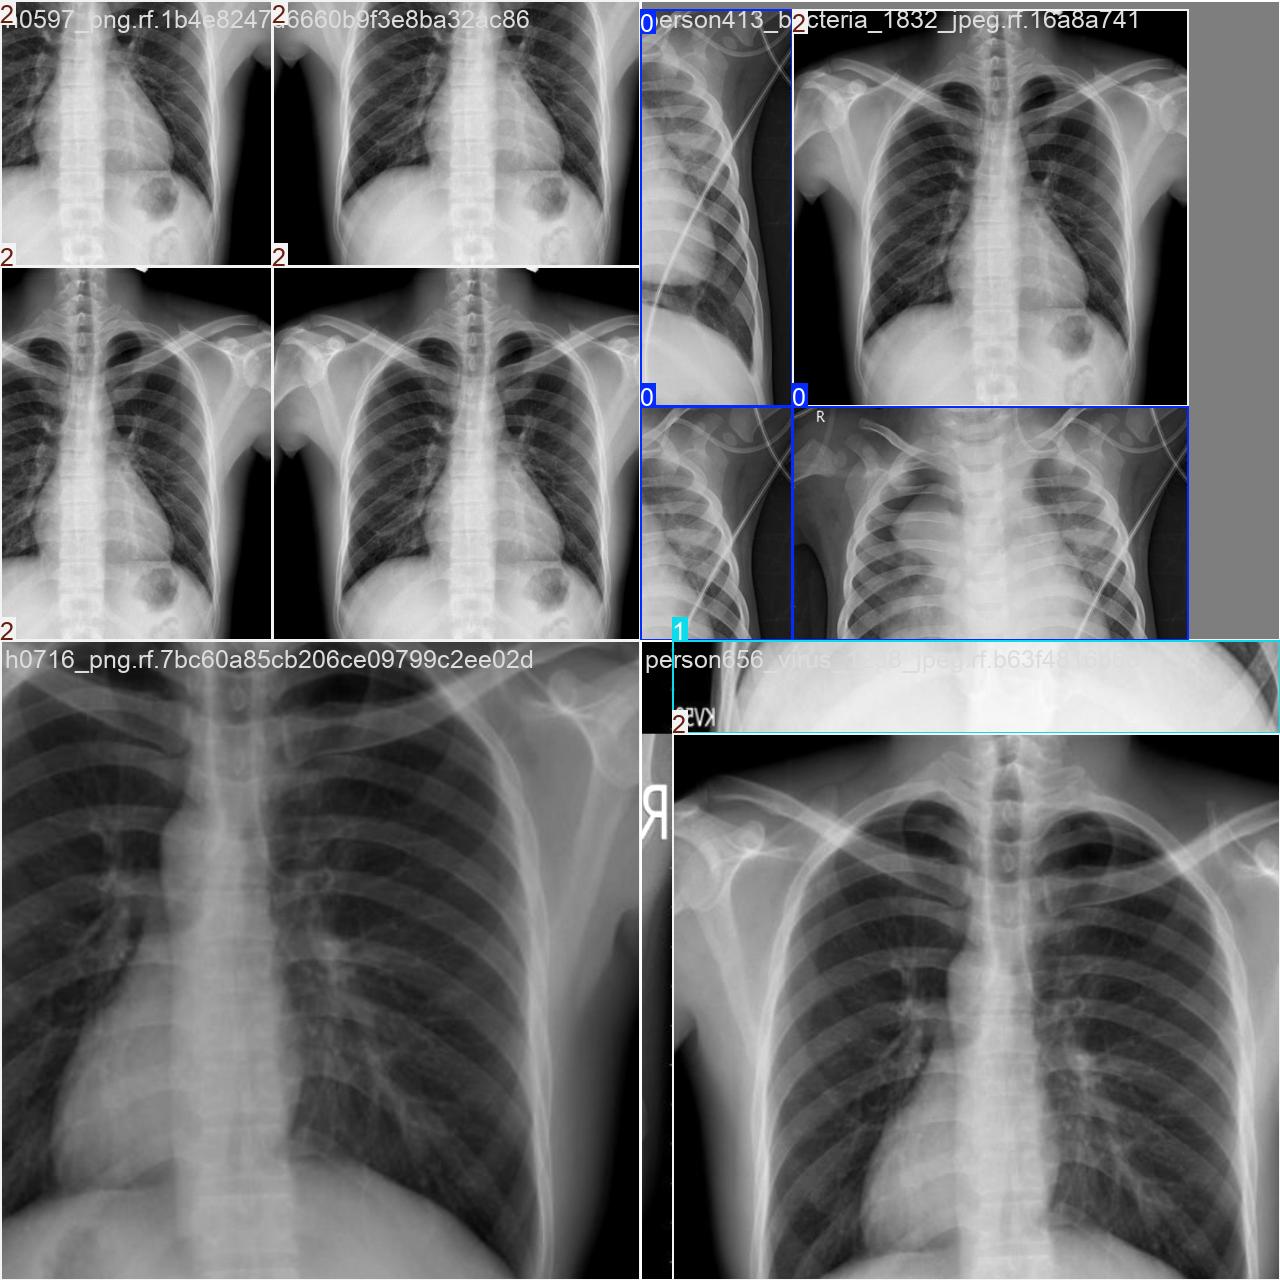

部分数据集图像如下图所示:

部分标注如下图所示: